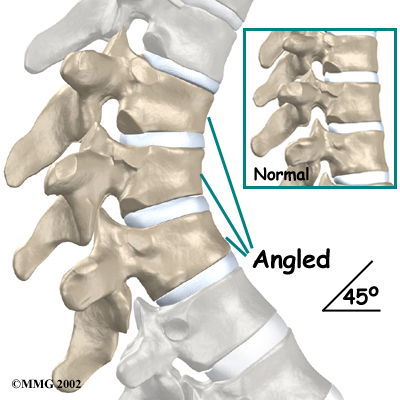

The angle of normal kyphosis in the thoracic spine varies. The angle increases slightly throughout life both in women and men. During the growth years of adolescence, a normal curve measures between 25 and 40 degrees. In general, kyphosis tends to be more exaggerated in girls. If the curve angles more than 40 degrees in either boys or girls, doctors consider the kyphosis a deformity. Scheuermann's disease causes the thoracic kyphosis to angle too far (more than 45 degrees).

In Scheuermann's disease, the front of the vertebral body becomes wedge-shaped, possibly from abnormal growth. This produces a triangular-shaped vertebral body, with the narrow, wedged part closest to the front of the body. The wedge creates a larger bend in the kyphosis of the thoracic spine.

Investigations

Taken from the side, an X-ray may show vertebral wedging, Schmorl's nodes, and changes in the vertebral end plates. Doctors use X-ray images to measure the angle of kyphosis. An official diagnose of Scheuermann's disease is made when three vertebrae in a row wedge five degrees or more and when the kyphosis angle is greater than 45 degrees.